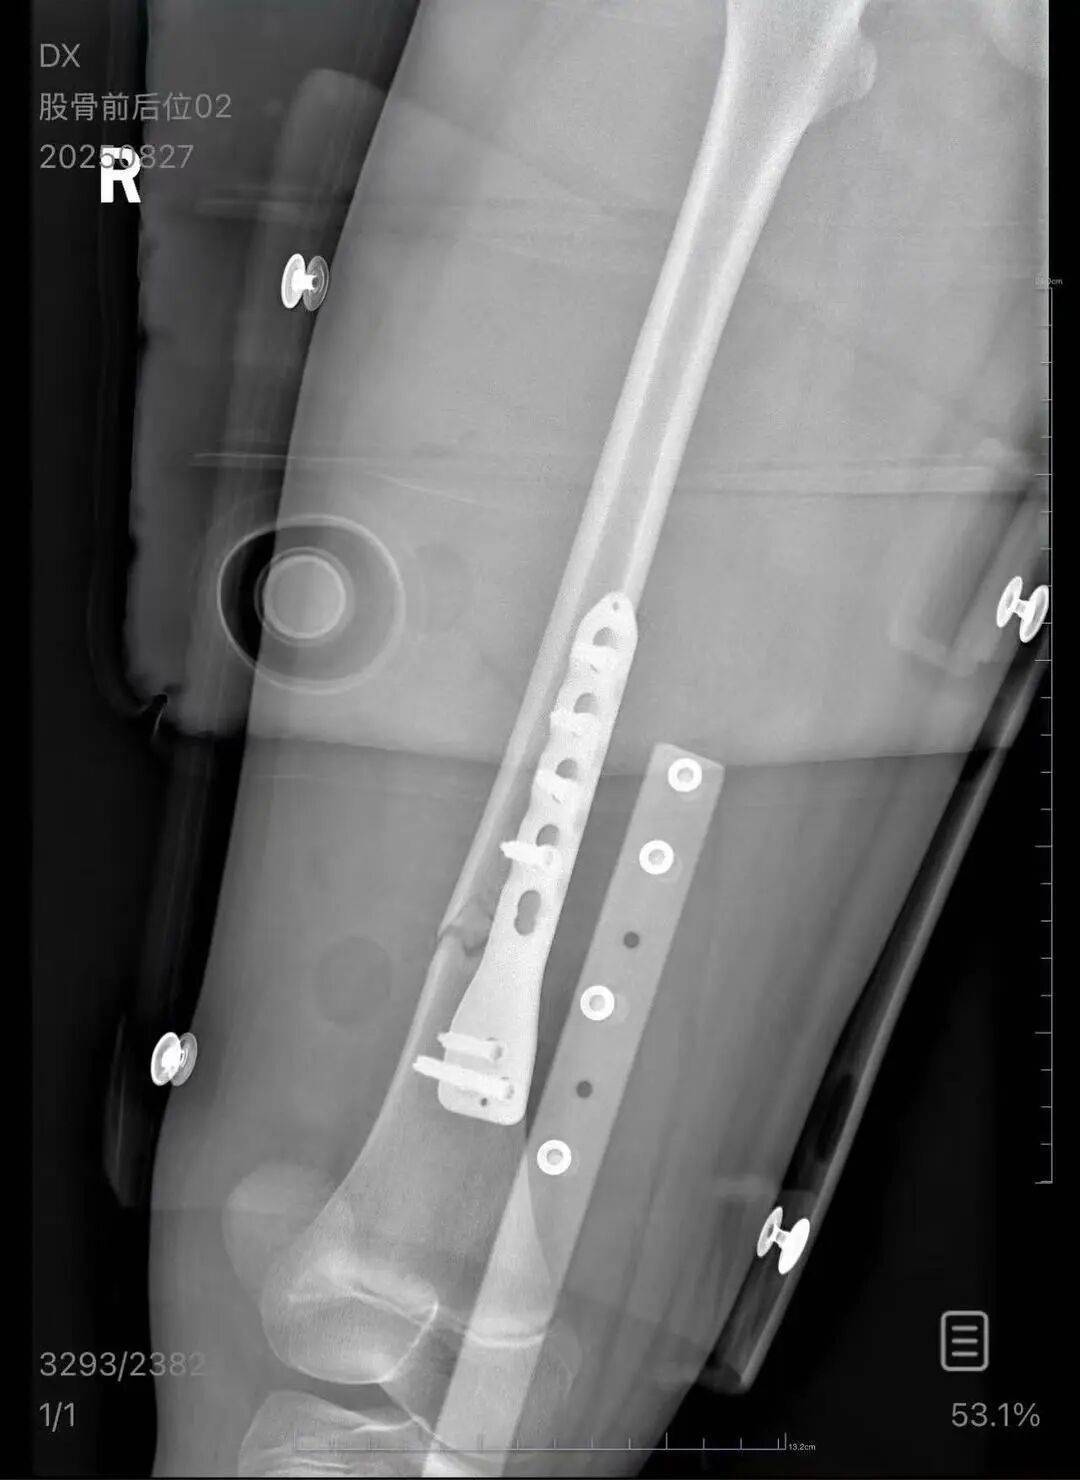

朱女士向记者出示的医院病历显示,8月24日凌晨,朱女士的女儿到医院就诊京东方a股票。医院诊断朱女士的女儿右股骨骨折,需要住院进一步治疗。

▲朱女士女儿手术后拍的X光片 受访者供图

朱女士出示的报警回执显示,8月24日凌晨2点22分,上海铁路公安处无锡站派出所接到报案京东方a股票。报案人称,在某列车上,快要到无锡站时,上铺的乘客下床时没抓稳,导致孩子大腿骨折。